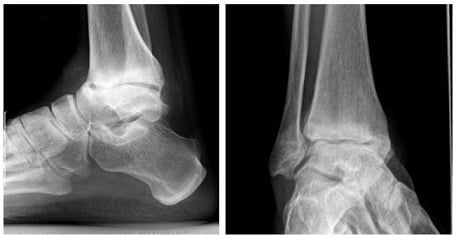

Для установления стадии артроза и получения более детальной информации о патологии используется рентгенография в 2 проекциях, УЗИ, КТ или МРТ сустава.

- На рентген-снимке можно отметить небольшое сужение суставной щели, если артроз на 1-й стадии.

- При переходе во 2-ю стадию суставная щель снижена на 40 % и более от нормы.

- На 3-й стадии она значительно сужена, может практически отсутствовать, видны разрастания и деформации костей.